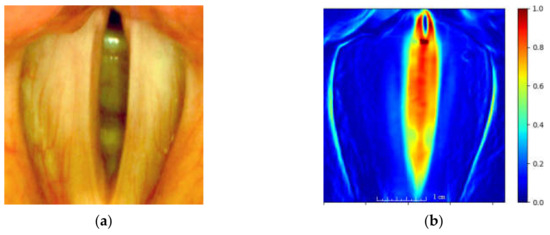

where: I x , y , t —is the intensity function of the image at spatial coordinates x, y, and t denotes the frame index t = [0, 1, …, N − 1] of N analyzed images from the LHSV sequence. Points of TV(x,y) map assume large values for those image locations where there is a large variability of image brightness for consecutive images of an LHSV sequence. The map serves to locate the ROI for further image analysis. Figure 7 presents the obtained heat map based on the established ROI.

Figure 7. The image of the glottis of a normophonic subject (a) and the corresponding total variation image (b), as defined in Equation (1), represented as a heat map (the larger the variation, the warmer the color of the map).